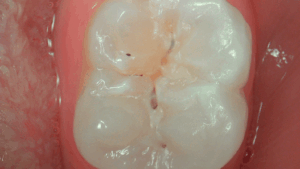

• Mode Daylight : Enregistrement des couleurs naturelles pour une interprétation de la teinte de la dent, une identification de la pathologie et un suivi du patient amélioré

• Mode Daylight+ : Contrastes élevés mettant en exergue les fissures anatomiques et les détails de la structure/ profondeur de la dentine.